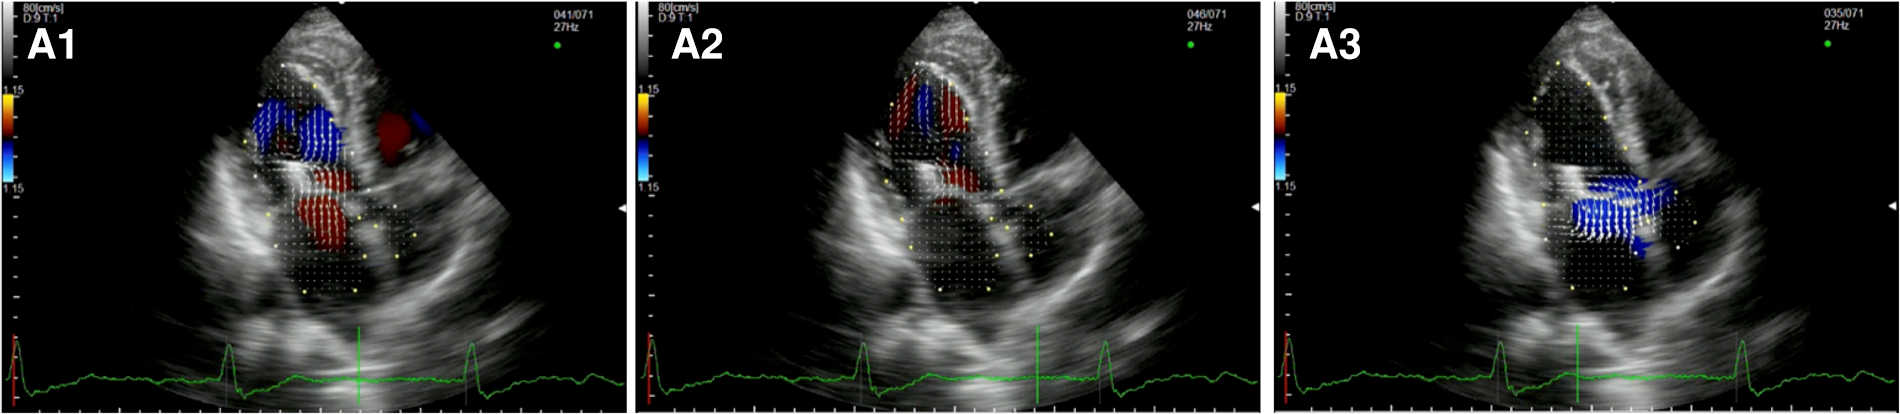

After TEER (Figure 4, Supplementary Video S7), during diastole, we observe multiple vortices without forming the typical main clockwise vortex occupying the center of the cavity. In systole, hemodynamic forces are partially restored along the LV longitudinal axis, from the apex to the LVOT, with an incomplete pair of counterrotating vortices in the left atrium due to the residual MR.

Figure 4

Apical long-axis view. Intracardiac flow vectors in early and late diastole (A1,A2) and mid-systole (A3) after transcatheter mitral valve repair with MitraClip (residual mild-moderate MR).

The three patients who underwent TMVR presented a nearly normal flow pattern (Figure 5, Supplementary Video S8). During early filling, we observed the formation of the typical two counterrotating vortices, with the major one below the AML pushing back the blood flow and redirecting it towards the LVOT during mid-systole.

Figure 5

Apical long-axis view. Intracardiac flow vectors in early and late diastole (A1,A2) and mid-systole (A3) after transcatheter mitral valve replacement with Tendyne system.